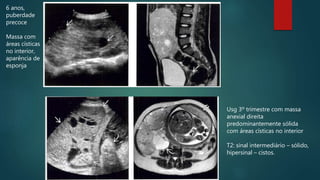

6 anos,

puberdade

precoce

Massa com

áreas císticas

no interior,

aparência de

esponja

Usg 3º trimestre com massa

anexial direita

predominantemente sólida

com áreas císticas no interior

T2: sinal intermediário – sólido,

hipersinal – cistos.